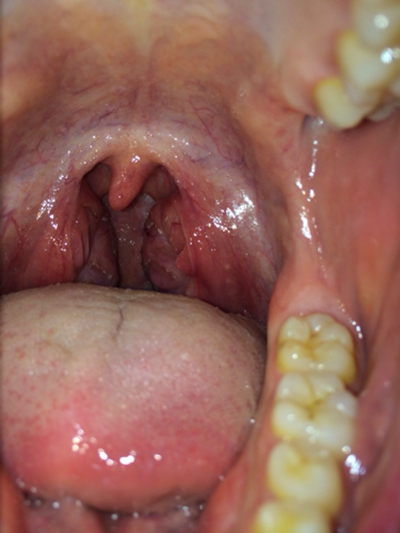

扁桃體炎圖片

扁桃體腫大